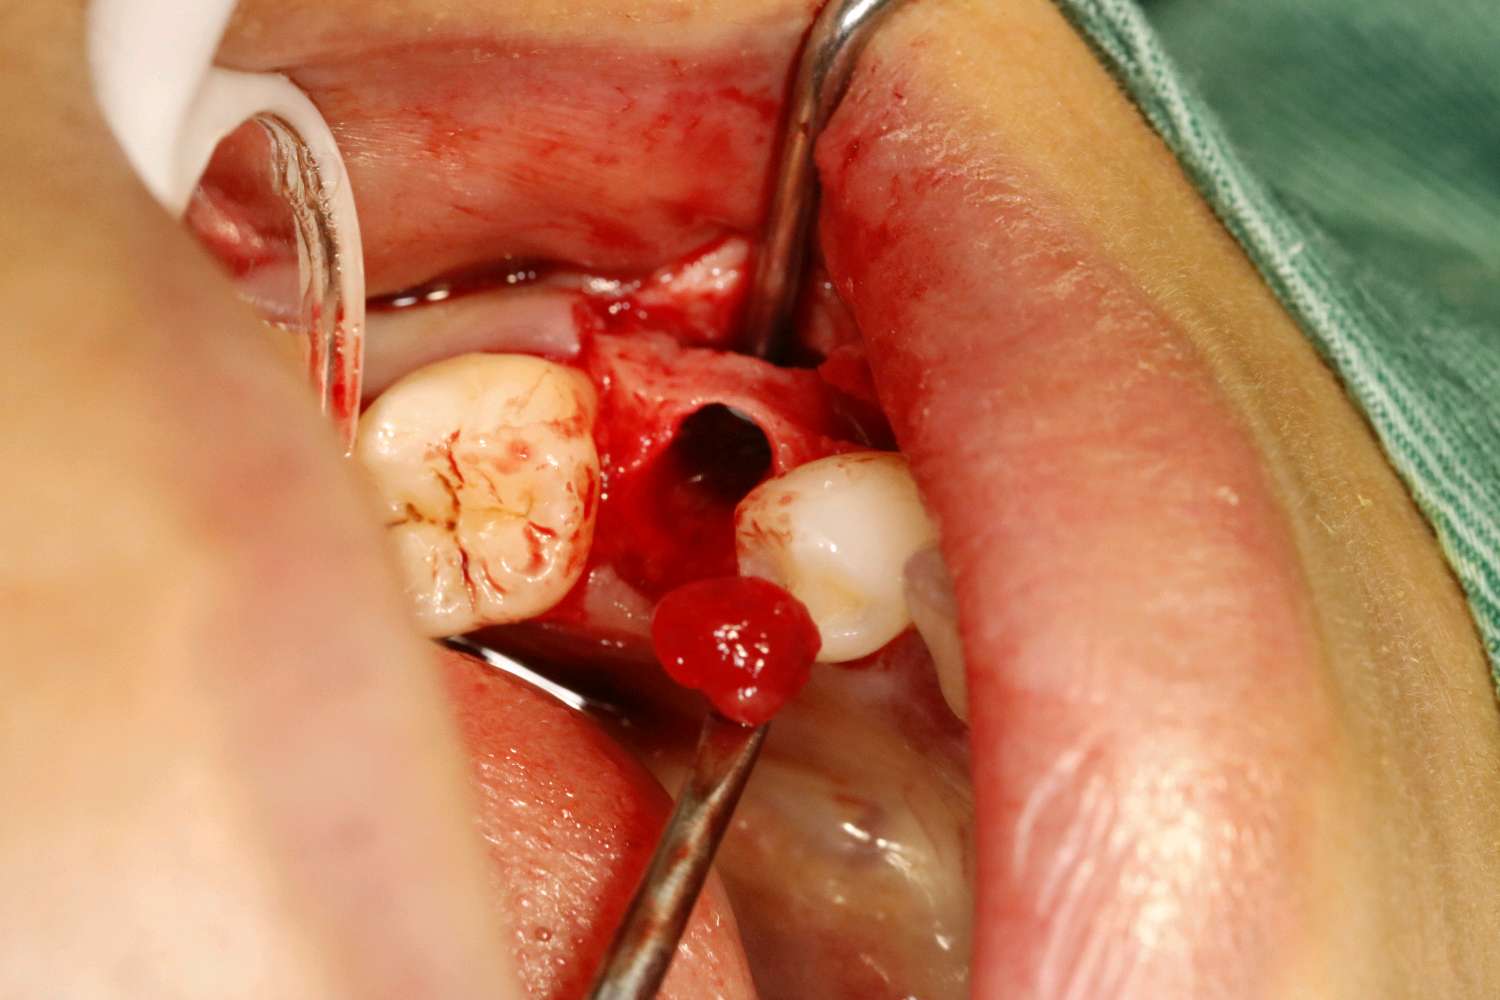

畸形中央尖多发生于下颌第二前磨牙,是一种牙体形态的发育异常,畸形中央尖本身不是什么大问题,只是折断或者磨穿了才会有不好的后果。这位患者就是因为没有长期的磨耗使的根尖周发生炎症时,导致根尖发育停止,根管口呈喇叭口状。对于这种牙根过短,根尖炎症范围过大的患牙,则考虑给予拔除。拔出后植入骨粉骨膜,后期种植修复。

术中